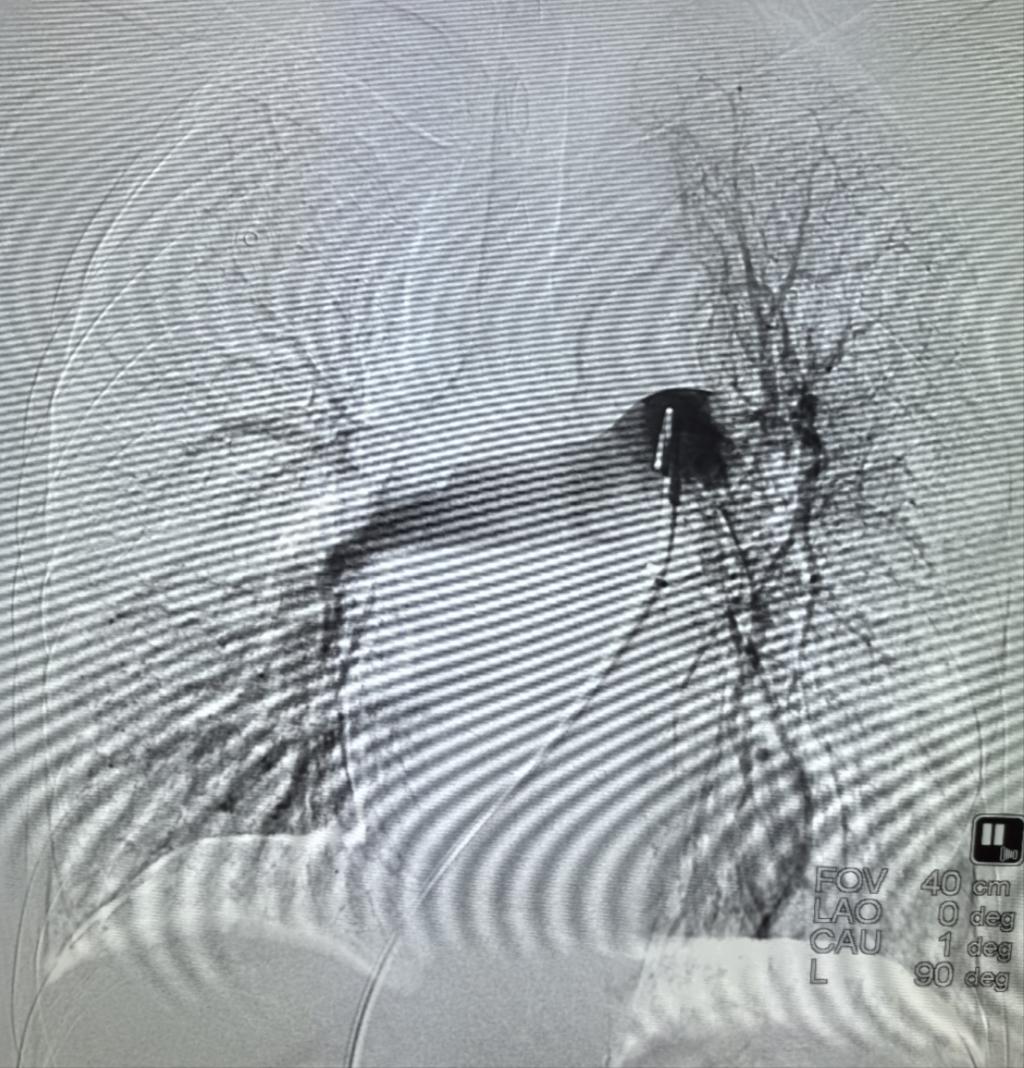

抽栓前造影

抽栓后造影

患者入院时,门诊CTPA提示:双肺动脉主干肺栓塞,伴有右心房栓子(性质不确定)、下肢深静脉血栓,经急诊抢救室初步评估为肺栓塞(高危)立即收住EICU。急诊科裴红红主任立即组织EICU李萍教授、急诊科介入团队彭卓副主任、古长维副教授评估患者后,决定给予患者行经导管肺动脉机械取栓术,这样不仅能够抽吸肺动脉栓子,同时能够明确右心房及肺动脉栓子性质。在影像科积极协助下,术中下腔静脉造影见下腔静脉血栓附着,通过精准定位行下腔静脉滤器置入。然后,肺动脉造影,见双肺显影不佳,左肺为著,测肺动脉压50mmHg,行肺动脉血栓抽吸术,术中明确栓子性质为血栓,行肺动脉造影,双肺显影明显改善,复测肺动脉压39mmHg,遂于肺动脉主干留置导管后持续24小时溶栓治疗。后续持续抗凝,患者症状明显改善,2日后转入普通病房,并自由活动,复查心脏B超:右心房未见血栓,现患者已康复出院。